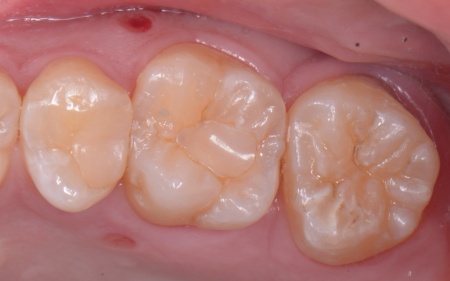

④矯正終了後に右上下奥歯の合わなくなった被せ物を除去し、自然な白さで強度もあるジルコニアセラミッククラウンを装着する。

最後に装着したジルコニアセラミッククラウンが歯に合っているか、噛み合わせに問題がないかを確認し、治療を終了しました。